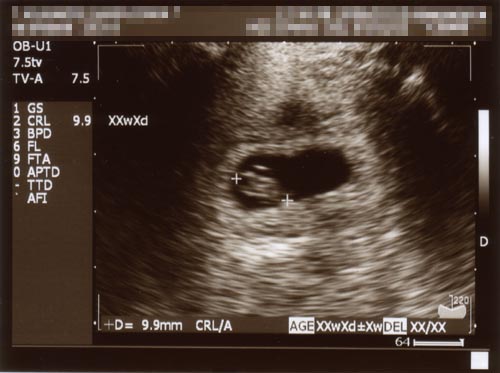

●2006.07.13(Thu)

昨日、妻と産婦人科へ行ってきました。

前回の超音波写真では小さすぎて出産予定日が確定しなかったので、

今回どれくらい大きくなっているのか、気になっていました。

今回の超音波写真を見てみると・・・・・・

(クリックすると拡大します)

大きくなってる~!!☆

前回の大きさは10.5mm。

これは胎嚢(たいのう)という袋の大きさでした。

今回の9.9mmは頭臀長、つまり赤ちゃんそのものの大きさなのです。

私は見ることができませんでしたが、

妻は診察の際、実際に動いている画面をみせられ、

心臓がパクパク動いている様子に感動。

待合室にいた私を見るなり、興奮ぎみに報告してくれました。

まだ妊娠初期ということで、

流産など気をつけなければならないことが多いのですが、

なんとか無事に過ごしてくれればいいなと思います。